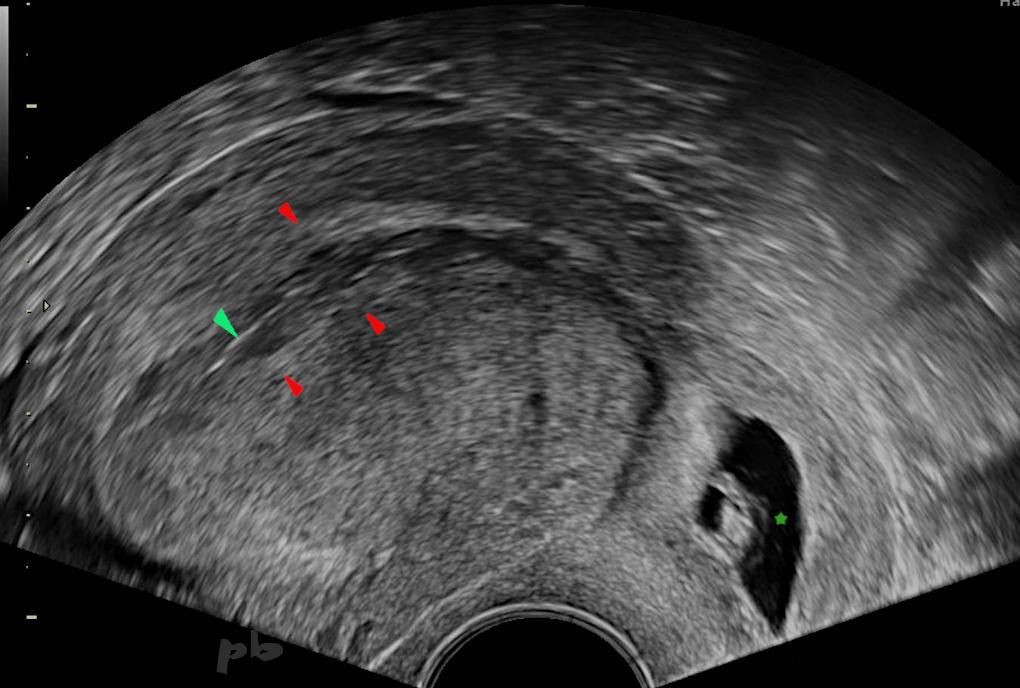

33- GEU interstitielle

Voie endo-vaginale.

Grossesse obtenue après stimulation ovarienne et réimplantation embryonnaire, située dans le segment interstitiel (ou intra-mural) de la trompe droite.

Pas de myomètre visualisé entre le bord utérin et le trophoblaste (►).

Sur l’image, on visualise le sac gestationnel en-dehors de la cavité.

Endomètre (►)

Embryon (★)

33- Interstitial Ectopic Pregnancy

Transvaginal ultrasonography.

Pregnancy achieved after ovarian stimulation and embryo reimplantation. The pregnancy is located in the interstitial (or intramural) segment of the right tube.

No myometrium visualized between the uterine edge and the trophoblast (►).

In the image, the gestational sac is visualized outside the cavity.

Endometrium (►)

Embryo (★)